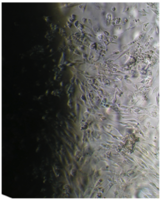

2 серия экспериментов. В культуральные чашки помещали образец исследуемого материала (кусочек недеминерализованной спонгиозы серии «Лиопласт»® объемом 125 куб. см), после чего высевали фибробласты в концентрации 20000 клеток/см².

Наблюдение через сутки показало, что фибробласты хорошо пристают к дну культуральной чашки, образуют равномерный монослой с плотностью 311 клеток/мм².

Фибробласты были распластаны по дну чашки, имели обычную для этих клеток удлиненную форму, 2-4 отростка, клеточная и ядерная оболочки четко контурировали.

Цитоплазма представлялась гомогенной (рис. 33). Большинство клеток имели одно центрально расположенное ядро правильной округлой формы с 1 или 2 ядрышками.

Количество поврежденных клеток -  3.